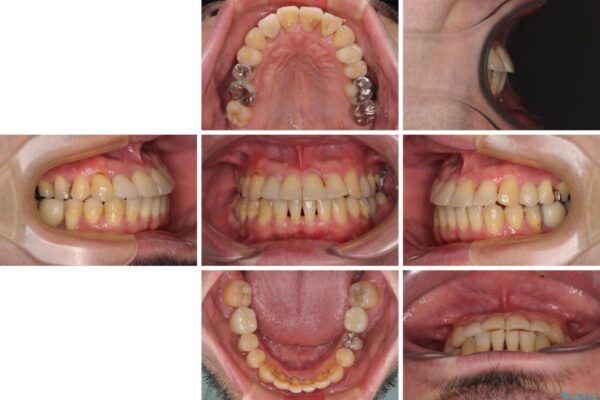

治療前

• 割れてしまった奥歯とデコボコの前歯 矯正治療とインプラント治療 治療前画像